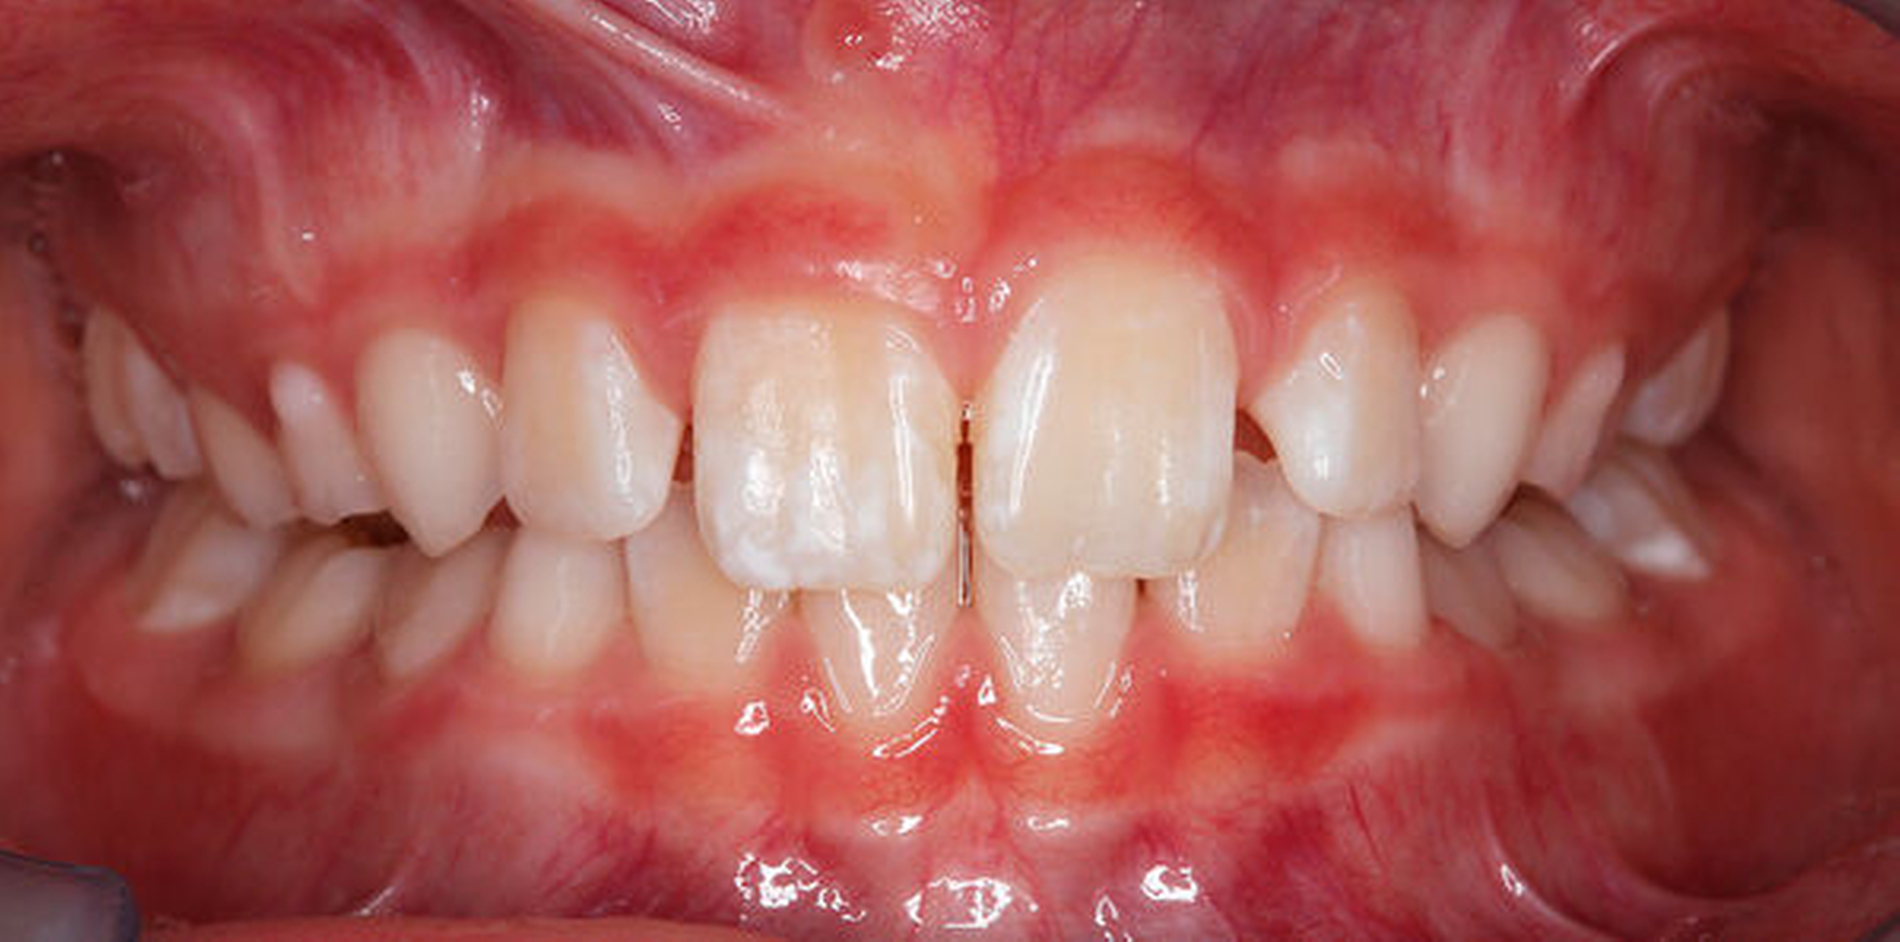

Die Dentalfluorose zeigt sich als Folge einer chronisch überdosierten systemischen Fluoridexposition während der Schmelzbildung und -reifung. Sie tritt symmetrisch an homologen Zahnpaaren gemäß den Mineralisationszeiten auf und ist eine von der Dosis abhängige Erscheinung [Fejerskov et al., 1990]. Für die Abgrenzung zur MIH sind die Anamnese und der klinische Befund entscheidend (Abbildung 5).